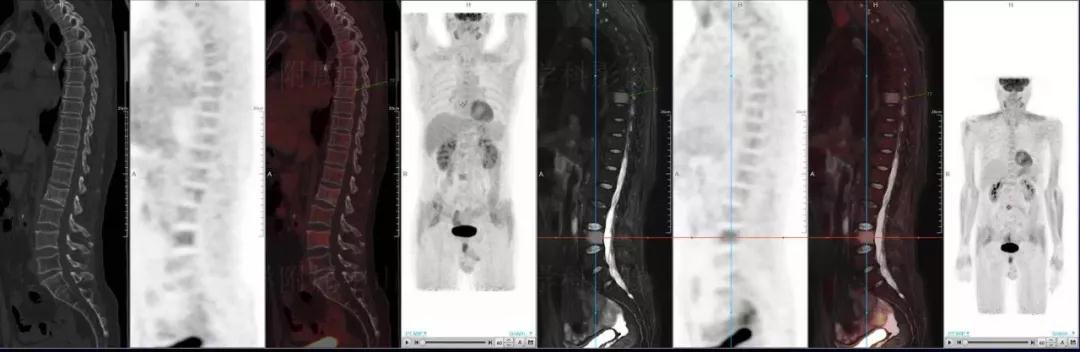

多發(fā)性骨髓瘤

中山醫(yī)院核醫(yī)學(xué)科基于聯(lián)影“時空一體”超清TOF PET/MR的融合顯像優(yōu)勢,進(jìn)行了大量的臨床掃描,發(fā)現(xiàn)多例由MGUS向多發(fā)性骨髓瘤轉(zhuǎn)變,并從中總結(jié)出了一定的共同征象,未來可能實(shí)現(xiàn)多發(fā)性骨髓瘤的早期篩查。此外,PET/MR在多發(fā)性骨髓瘤的療效評估方面,也存在顯著優(yōu)勢。

(男性,53歲。確診多發(fā)性骨髓瘤10月。經(jīng)過7周期VCD方案化療后,現(xiàn)行療效評價。)